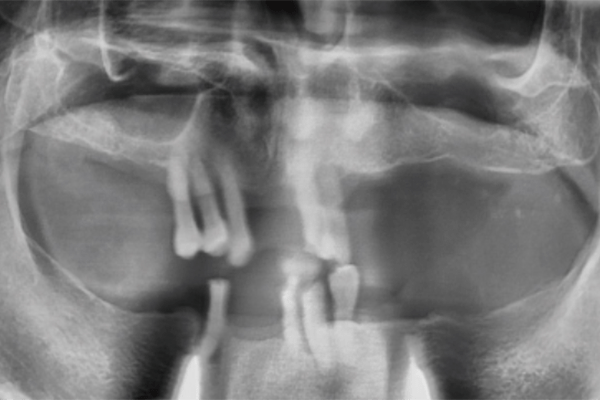

鈕扣式植牙(周先生)